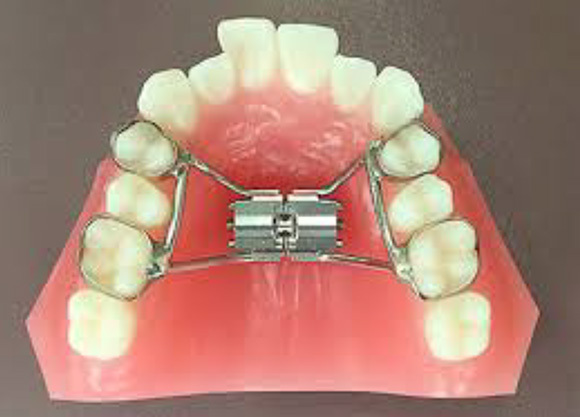

固定式拡大装置は床タイプと違って自分で外せないので、確実に治療が進みます。 また床タイプでの拡大では傾斜移動になり根尖が動きませんが、固定式の場合は歯体移動ができ、鼻腔も広がる可能性があり口呼吸から鼻呼吸への改善可能性があります。